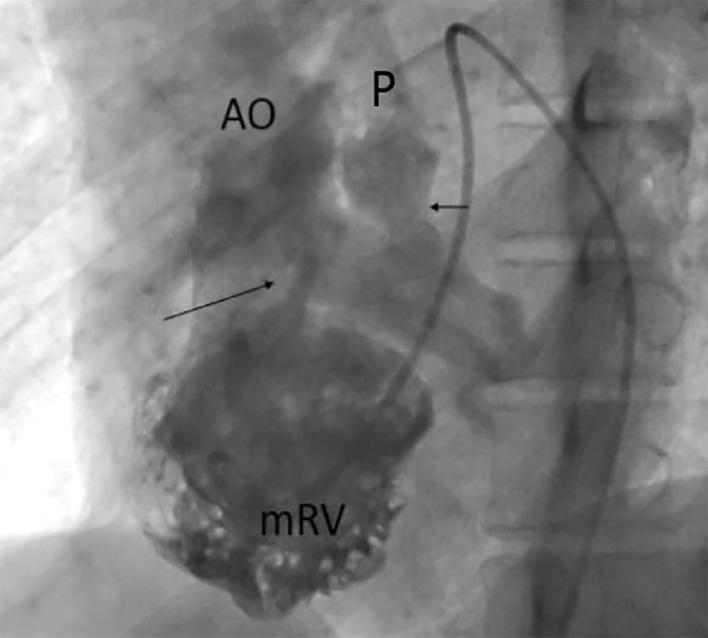

Situs inversus with levocardia and congenitally corrected transposition of the great arteries represents a relatively very rare congenital condition and most patients are diagnosed in infancy or early age. This case report describes a 35-year old man with congenitally corrected transposition of the great arteries which presented with a five month history of exertional dyspnea. A diagnosis was confirmed by transesophageal echocardiogram, showing situs inversus, levocardia, atrioventricular and ventriculoarterial discordance. He underwent physiologic repair, and was discharged thirty five days after the operation, in a good general condition. Although management of the corrected transposition of the great arteries patients remains controversial, the recommendation is that physiologic repair may be the procedure of choice for some patients, particularly complicated cases.

镜像右位心伴左位心及先天性矫正型大动脉转位是一种相对非常罕见的先天性疾病,大多数患者在婴儿期或幼年时被诊断出来。本病例报告描述了一名35岁男性,患有先天性矫正型大动脉转位,出现劳力性呼吸困难5个月病史。经食管超声心动图确诊,显示镜像右位心、左位心、房室和心室动脉不一致。他接受了生理性修复手术,术后35天出院,全身状况良好。尽管先天性矫正型大动脉转位患者的治疗仍存在争议,但建议生理性修复可能是某些患者,尤其是复杂病例的首选手术方式。